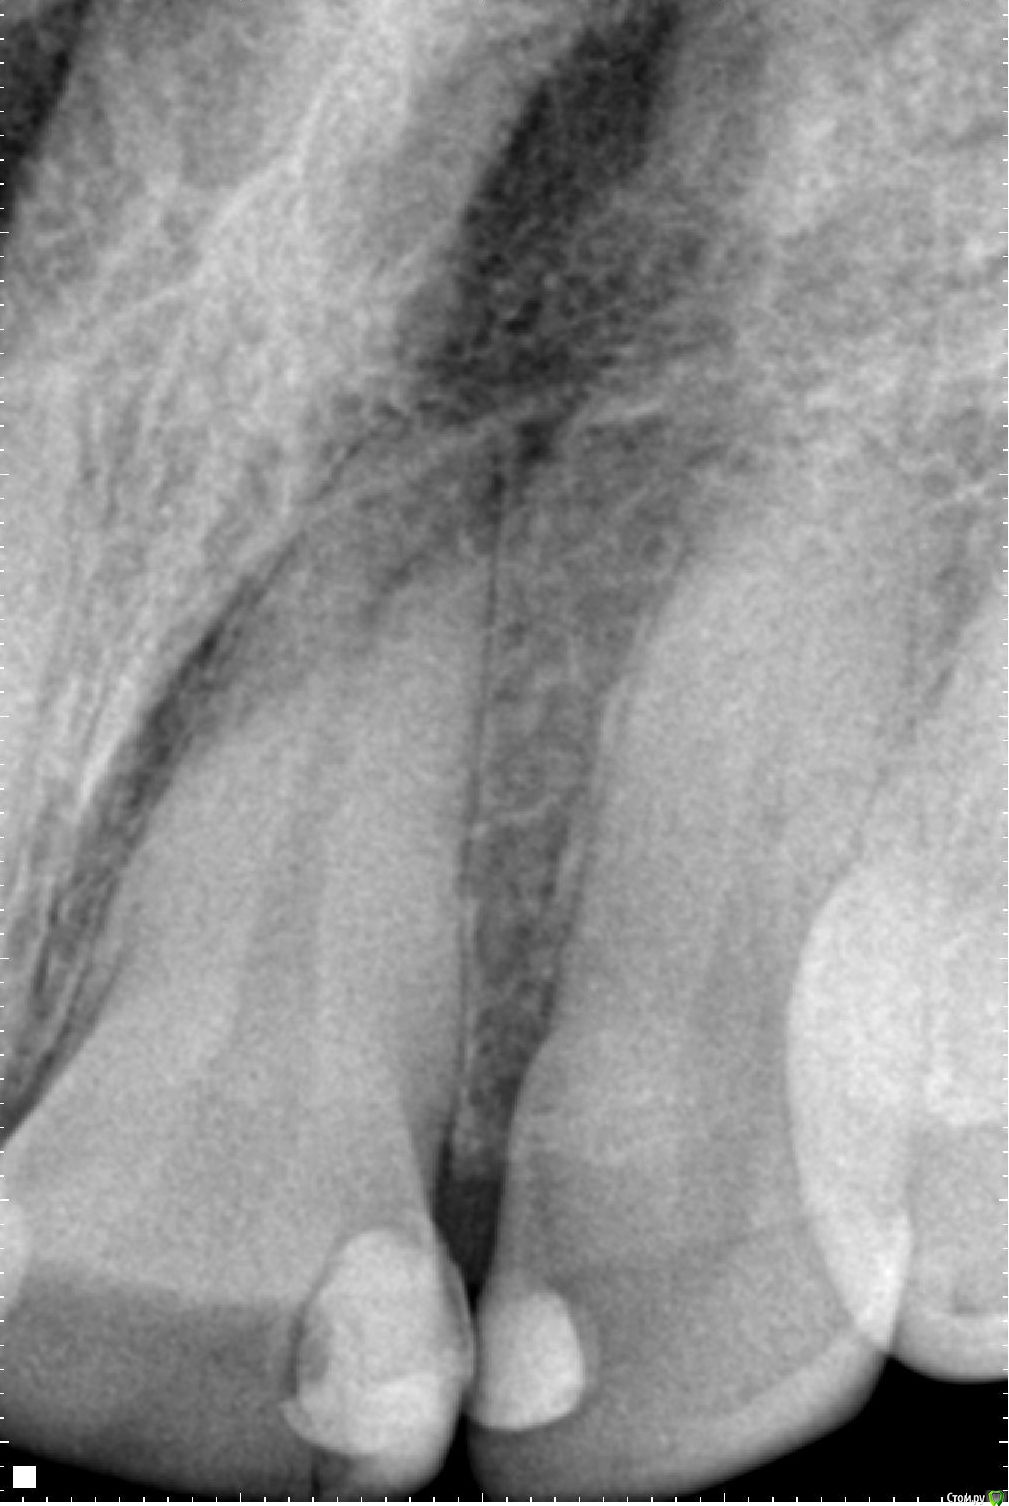

eizo Опубликовано 5 января, 2015 Поделиться Опубликовано 5 января, 2015 (изменено) Уважаемые специалисты и просто знатоки, помогите определиться по снимку на счёт наличия кариеса в 21м и/или 22м зубах. .Только что сделал снимок участка между 21м и 22м зубом (хотя снимок непонятный получился на мой взгляд).У меня уже 7 лет пломбав частив 21го зуба ближе к краю на границе с 22м. В середине ноября треснул 21й с нижней кромки, но болевых ощущений не было. Стоматолог в районнной ничего не смог предложить, ничего не обнаружил. Перед новым годом начали проявляться неприятные ощущения после приёма пищи, причём по собственным ощущениям именно на краю 22го со стороны примыкания к 21му.Сходил в другую клинику, терапевт сходу предположил рецидив кариеса в 21м, отвергая какие-либо дефекты в 22м.На снимке вроде бы ракурс с внутренней стороны челюсти (снимок производился с датчиком).Насколько я могу разобраться на 22м наблюдается дефект. А вот на счёт 21го -там где светлое пятно - это должна быть пломба. Изменено 5 января, 2015 пользователем eizo Ссылка на комментарий

SDC Опубликовано 5 января, 2015 Поделиться Опубликовано 5 января, 2015 Не самые лучшие фото и рг снимок, но однозначно есть дефект пломбы 21 зуба (нависание в придесневой области)и я почти уверен в том ,что есть рецидив кариеса. По 22 зубу - ничего сказать не могу. Ссылка на комментарий